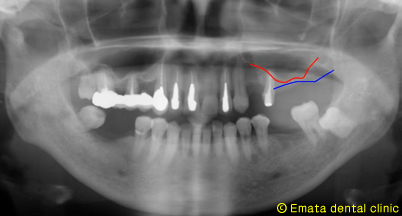

先週サイナスリフトと同時に3本インプラントを埋入しました。

サイナスリフトとは、上顎の奥歯にインプラントをしたくても上顎洞が低い位置にあるためインプラントを埋入するための骨が足りない人に行う手術です。この手術を初めて行った時はかなり神経質になってたことを思い出しますが、最近は慎重には行いますが、過剰にナーバスになるようなことはありません。

サイナスリフトをしてインプラントを埋入したところです。ポイントはいかに初期固定できるかです。 |

無事にインプラント埋入を終了した後の画像です。黄色いライン部分がサイナスリフトをした部分です。 |